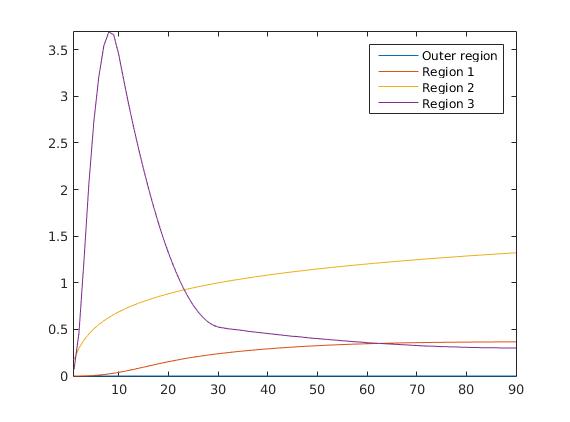

To test our reconstruction method, we created different synthesized data sets consisting of pixels with varying complexity of the image structure and with a different number of subregions and a total of 90 time steps in each sequence. Based on these subregions, we created three-dimensional matrices containing the true image in one time step within each slice. The underlying concentration in each subregion is related to a realistic shape of a the time-dependent behaviour of the tracer in different tissue types.

The first data set consists of a heart-shaped region and three circles on a static background (see figure 1 (a)). The two smaller circles are assumed to belong to

the same tissue type and therefore to the same subregion, which causes a total of four subregions, including the background. To simulate a more realistic application of dynamic SPECT

imaging, we used a synthesized representation of a rat liver as a second data set (see figure 1 (b)). The temporal concentration curves used to simulate the data sets

are shown in figure 2. As before, the total number of subregions was chosen to be equal to four in order to provide a both simple and realistic shape model.